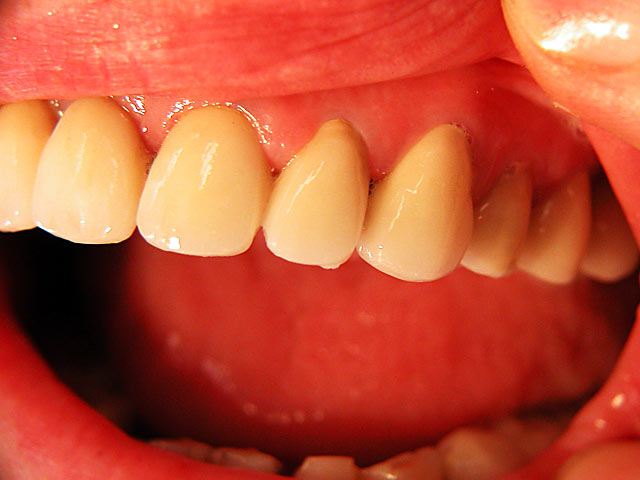

Frontzahn-Implantation: